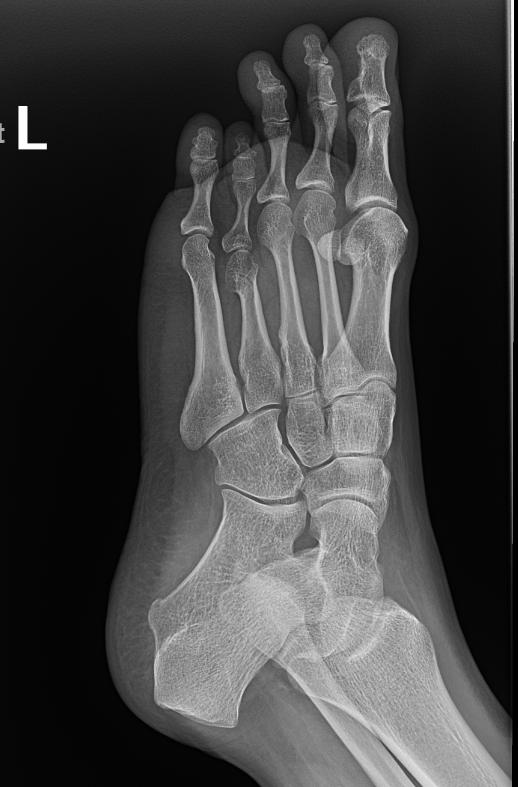

The initial assessment involves detailed history examination and review of previous x-rays. Specialized x-rays are usually required to complete the assessment. The initial assessment and discussion often takes an hour.

During the adjustment phase the patient is followed up in the rooms every two weeks with clinical examination and x-rays. A close scrutiny is maintained to identify any complications early.

During the adjustment phase, the patient is followed up in the rooms every two weeks with clinical examination and x-rays. Close scrutiny is maintained to identify any complications early.